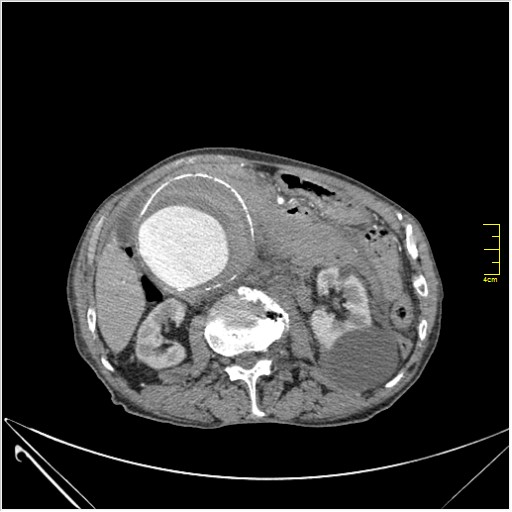

КТ брюшной полости. Мужчина с пальпируемой опухолью в животе

Пациент Т. 64 года, обратился на КТ брюшной полости амбулаторно (!), по направлению семейного врача с диагнозом abdominal mass, буквально: образование брюшной полости.

ИМХО простые кисты.Uzgraph писал(а):Случай интересный - ногу сломишь. Вроде бы анефризма брюшной аорты(особенно по УЗИ), но что тогда за образования сидят на левой почке - онкология?

Huge abdominal aorta aneurism. Simple renal cortical cysts (Bosniak type 1).